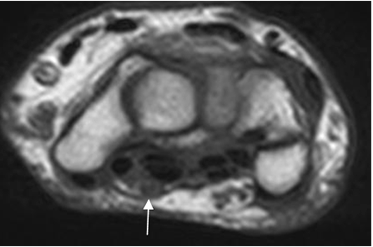

En la muñeca se identifican 2 retináculos, cuya función es mantener la posición de los huesos del carpo y contener los tendones flexores y extensores durante el movimiento. (9).

El retinaculo flexor o ligamento transverso del carpo se localiza entre el pisiforme y la apófisis del ganchoso en la parte lateral y el escafoides y el trapecio en la medial.

El flexor o ligamento dorsal del carpo se extiende desde los huesos piramidal y pisiforme, hasta el radio distal. (9). (Fig 32).

Fig 32. Retináculos.

A: RM axial en T1. Retináculo flexor normal.

B: RM axial en T1. Retináculo extensor normal.

El nervio mediano ocupa una posición superficial y medial del canal del carpo, entre los tendones del flexor superficial de los dedos y el flexor ulnar del carpo. Es una estructura con señal hipointensa y rodeada por grasa, mejor vista a nivel de la apófisis del ganchoso. (9). (Fig 33).

Fig 33. Nervio mediano.

RM axial en T1. Nervio normal, en la parte superficial del canal del carpo.